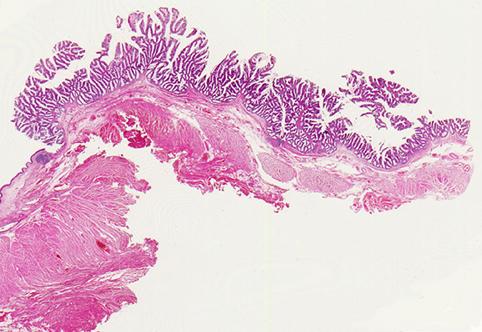

疾患(病理主体)の分類悪性上皮性腫瘍/腺癌

部位(臓器別)大腸/直腸

検査方法ミクロ

腫瘍の肉眼分類0型(表在型)/その他

病変の最大径(ミリ)40以上

腫瘍の深達度m